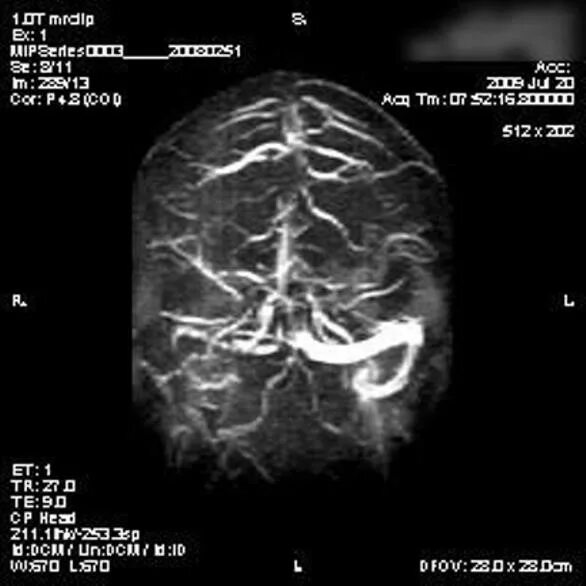

Что значит вариант развития виллизиева круга